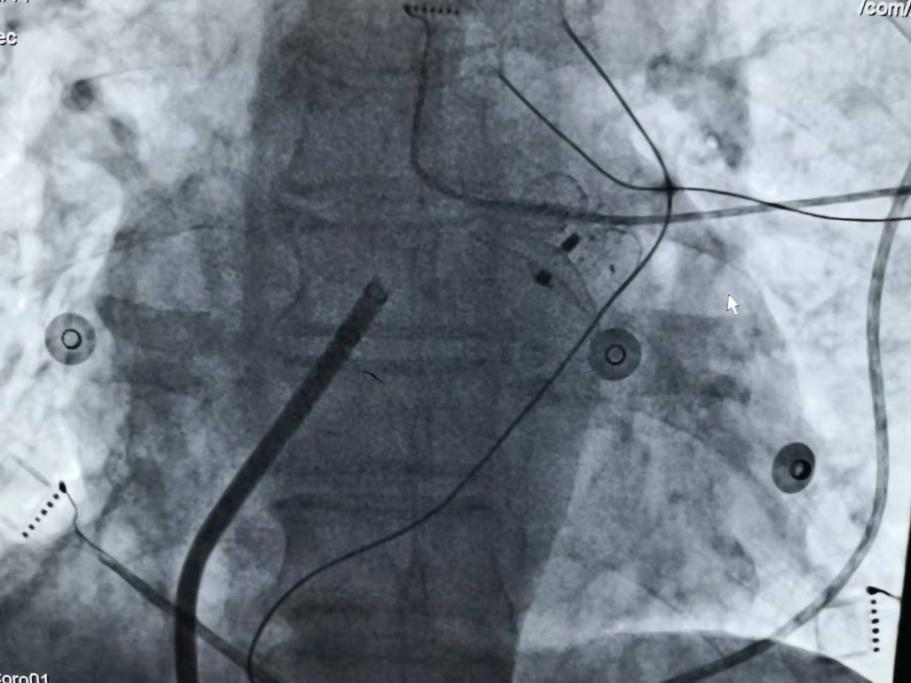

钱阿姨今年83岁,明确“阵发性房颤”十年,合并有高血压,慢性胃炎,甲状腺功能减退,腔隙性脑梗塞等疾病,十年来房颤发作越来越频繁,间隔时间越来越短,每次发作持续时间越来越长,并出现了心力衰竭,冠脉造影排除冠心病。

入院后,市九院心脏中心心血管内科一病区袁清茹主任、胡号兵副主任医师详细询问病史了解病情,钱阿姨为阵发性房颤病史长,已导致心功能不全,给患者日常生活带来严重的困扰,心理负担重,焦虑,失眠,患者因患有甲状腺功能减退,不适宜应用治疗房颤常用的胺碘酮,为预防血栓既往服用抗凝药物后出现皮肤瘀斑,牙龈出血,泌尿道出血等。心脏中心主任、心血管介入中心主任赵明中博士查看患者后指出:该患者长期受房颤严重困扰,心脏较前轻度增大,出现了心功能不全症状,且房颤发作自觉症状明显并造成严重心理负担,且老年患者,合并多种疾病,治疗需个体化。心脏彩超提示心房轻度增大,适宜射频消融术恢复正常的窦性节律、控制快速房颤发作症状;根据CHA2DS2-VASc评分6分,血栓栓塞风险高,HAS-BLED评分4分,抗凝出血风险高,须防治血栓栓塞,且患者不能耐受抗凝治疗,有明确左心耳封堵术适应证,建议射频消融术加左心耳封堵术一站式手术,患者本次住院的主要目的也是希望在郑州市九院心脏中心能用先进的心血管介入技术来帮助自己解除多年的疾病困扰。